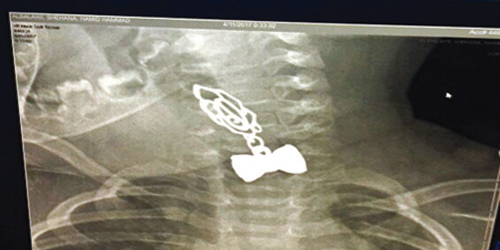

نجح فريق طبي بمستشفى الملك خالد بتبوك في إنقاذ حياة طفل عمره 8 شهور ابتلع سلسالاً معدنياً، وجاء تدخل الفريق الطبي بعد تحويل الطفل من مستشفى الوجه إلى مستشفى الملك خالد حيث أجريت له الفحوص الطبية وتبين وجود سلسال معدني أغلق مجرى الطعام، وعلى الفور، قام الفريق الطبي باستخراجه، وحالة الطفل الصحية جيدة ولله الحمد.